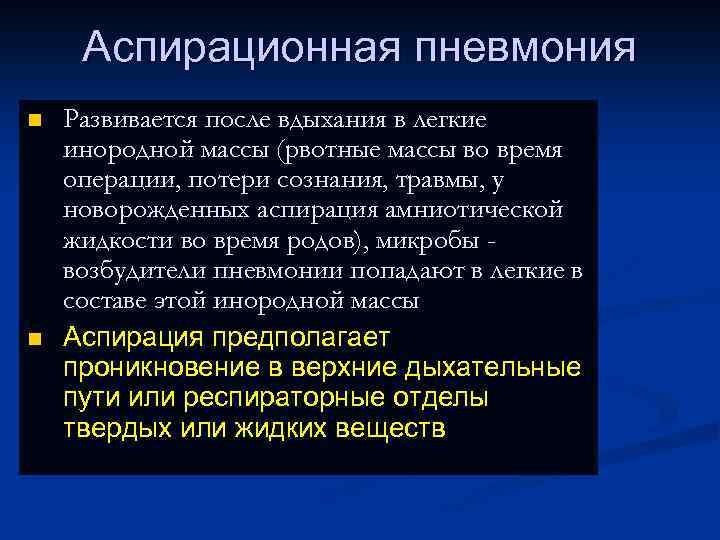

Аспирационная пневмония n n Развивается после вдыхания в легкие инородной массы (рвотные массы во время операции, потери сознания, травмы, у новорожденных аспирация амниотической жидкости во время родов), микробы возбудители пневмонии попадают в легкие в составе этой инородной массы Аспирация предполагает проникновение в верхние дыхательные пути или респираторные отделы твердых или жидких веществ